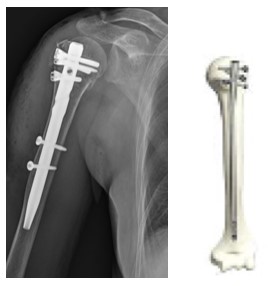

粉砕した骨折でもロッキングプレートにより早期リハビリが可能になりました。

ロッキングプレート

髄内釘

転位が少なければ髄内釘で固定します。